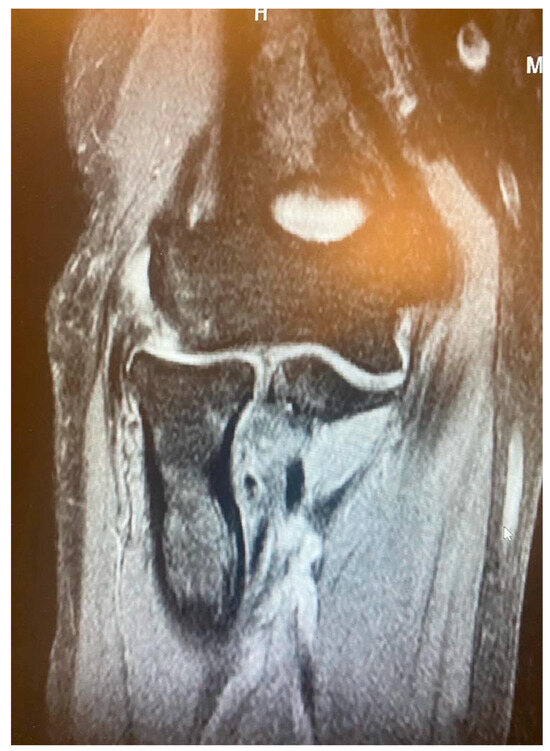

- It is contingent on the integrity of the CEO, whether it is intact, has a moderate or extensive partial tear, or is completely ruptured with or without retraction. This evaluation can be conveniently conducted via MRI.